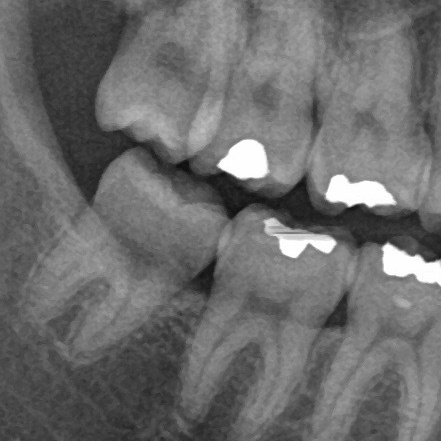

むし歯の親知らずは、削って詰める治療はできないの?

親知らずはお口の最も奥にあり、削る器具が届かない場合が多く、なんとか届いたとしても、どうしても治療が不十分になりがちです。

また、例え治療で親知らずのむし歯をすべて除去できたとしてもまたむし歯になる可能性が高く、削って詰める治療はオススメできないことがほとんどです。